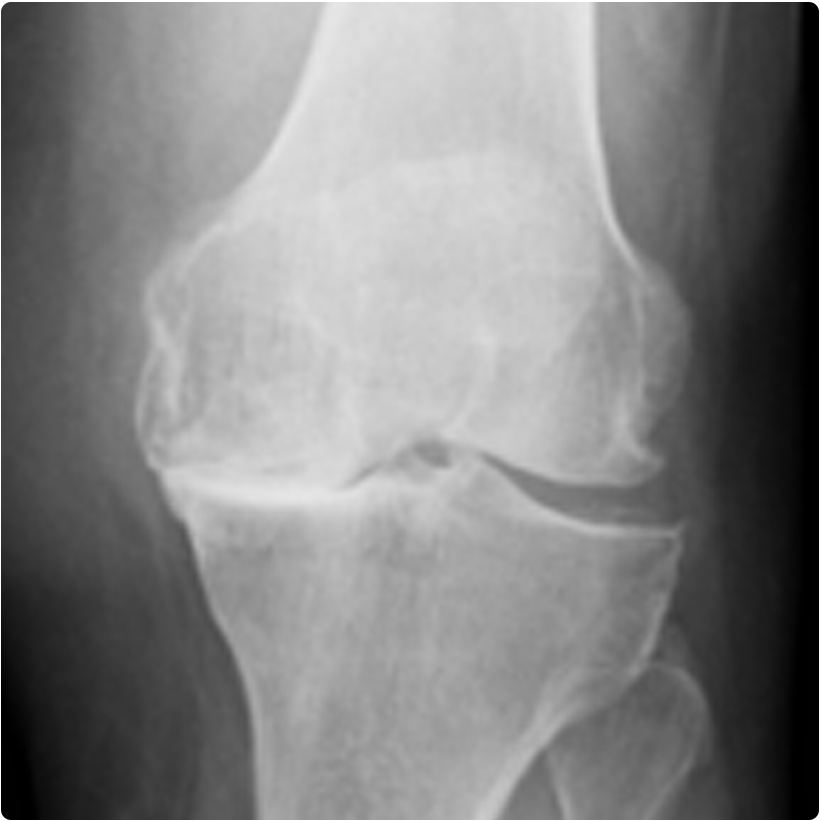

Ayrıca hastanın dizinin sadece bir bölgesi bozulduğunda, özel bazı durumlarda kullanılabilen parsiyel (kısmi) diz protezi de vardır. Resimde diz ekleminde osteoartriti olan bir hastanın ameliyat öncesi ve total (tam) diz protezi uygulandıktan sonraki diz röntgen grafileri görülmektedir.